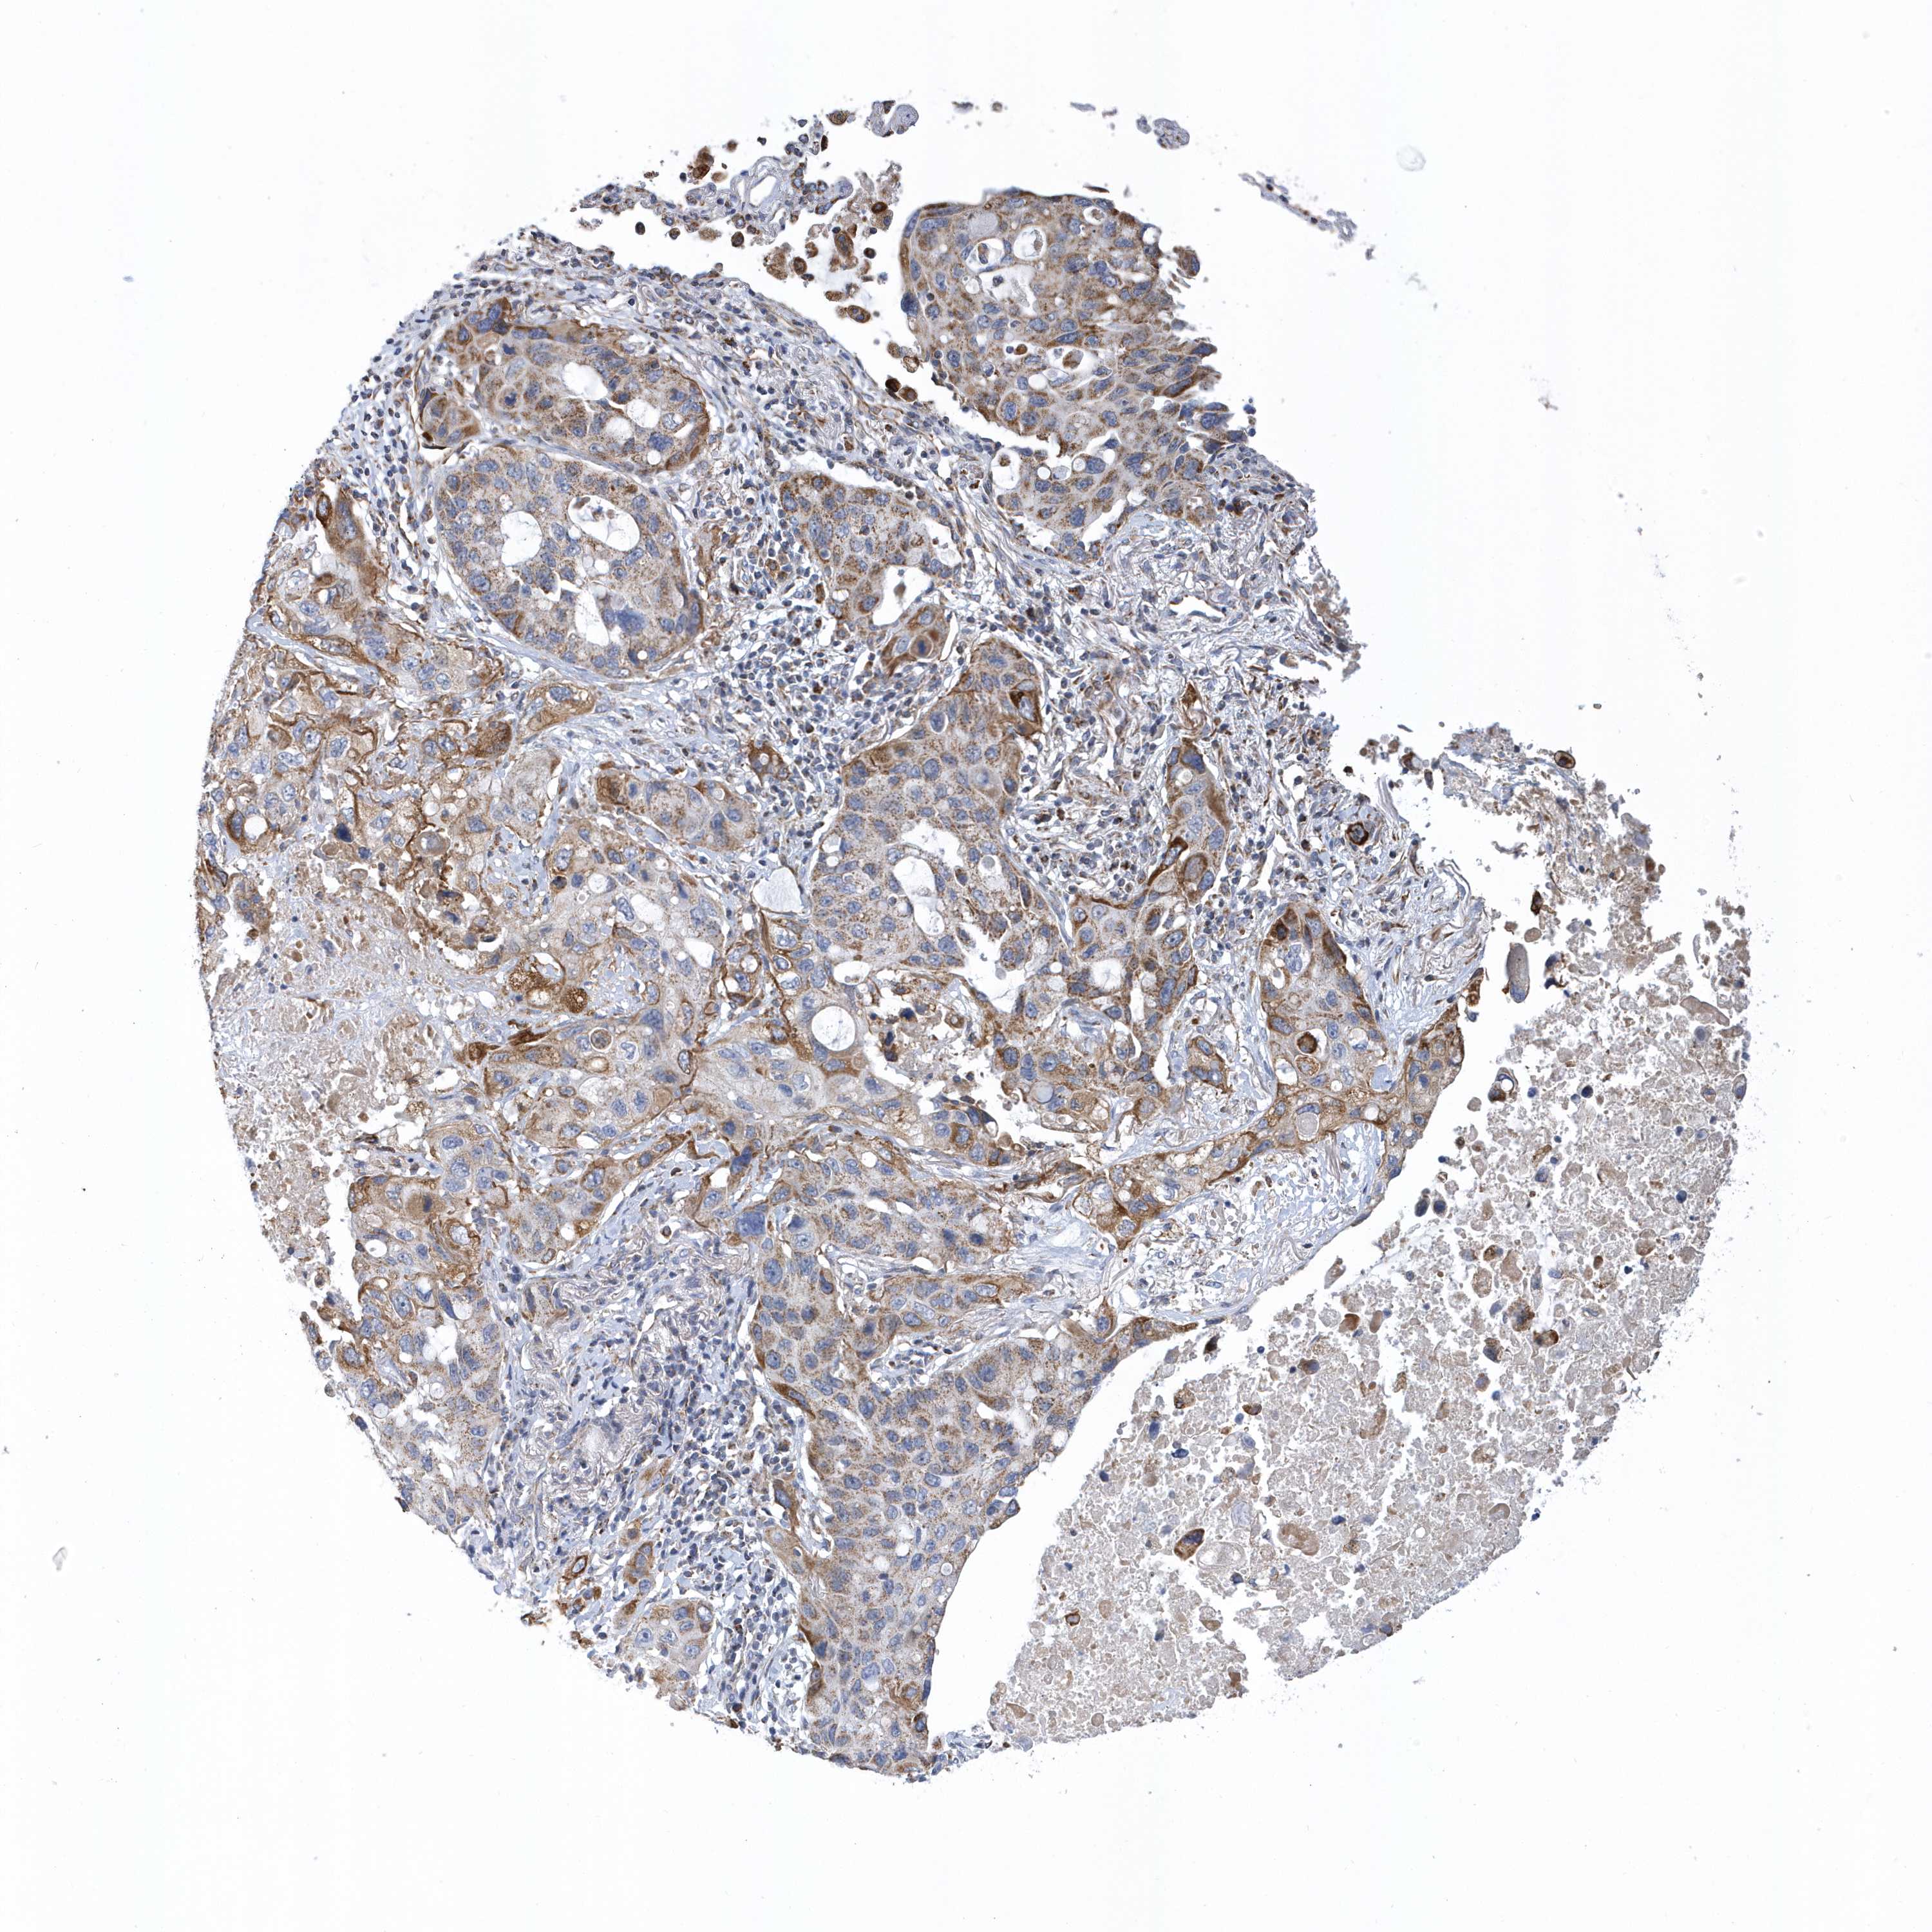

VWA5B2

CANCER LUNG CANCER Show tissue menu

LUAD TCGA LUAD VALIDATION LUSC TCGA LUSC VALIDATION PROTEIN LUAD CPTAC PROTEIN LUSC CPTAC PROTEIN EXPRESSION

Lung cancer

Human cancer